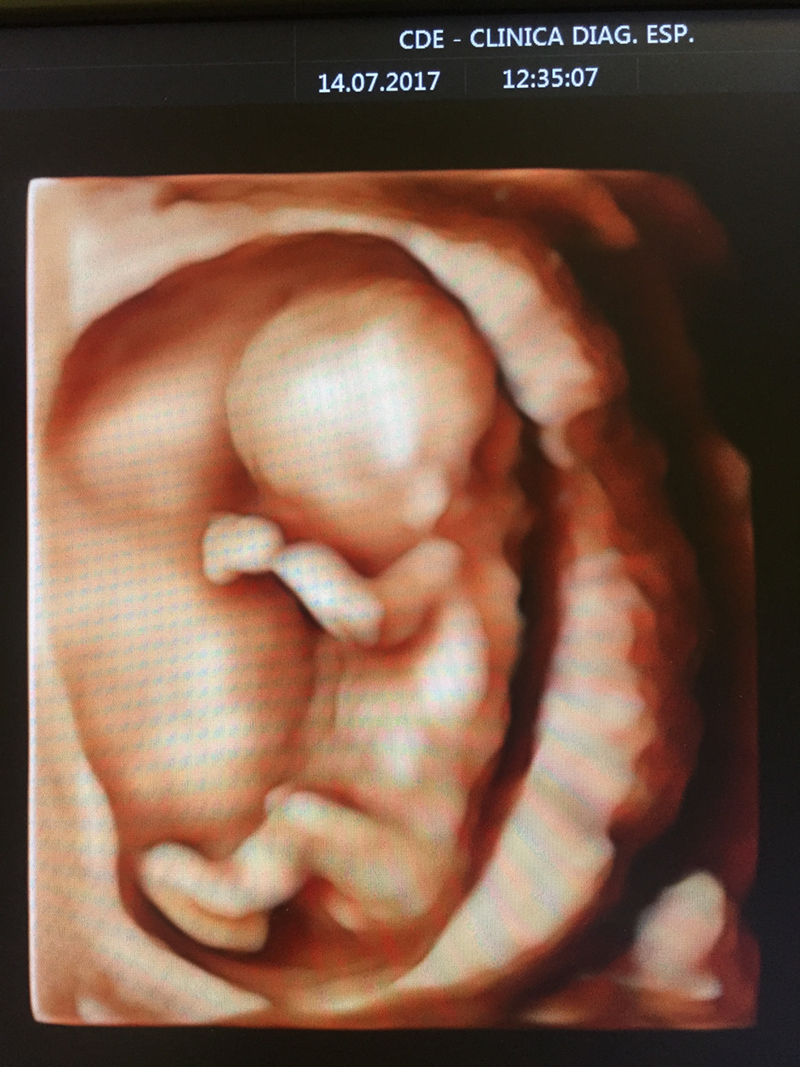

- Ultrassonografia Tridimensional 4-D;